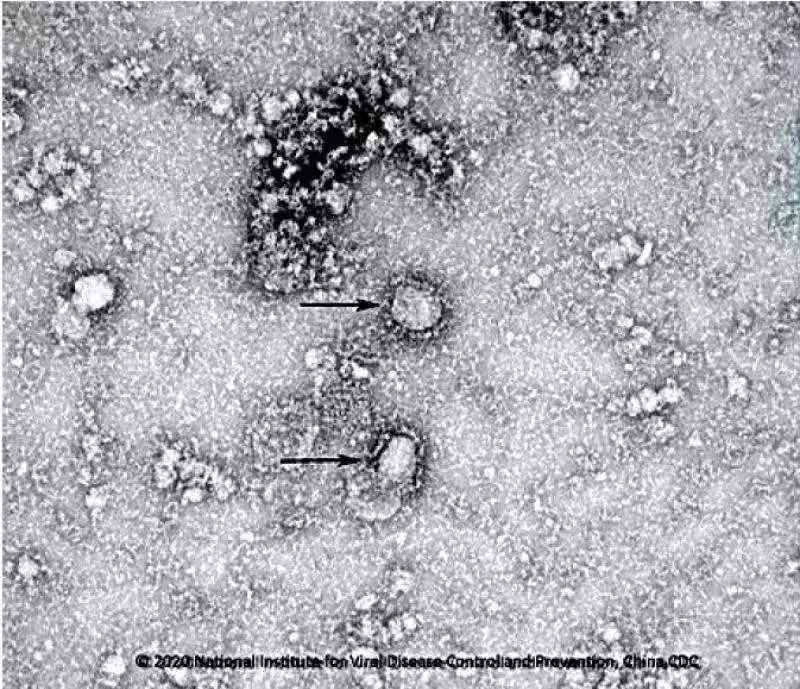

好消息!中國疾控中心成功分離我國首株新型冠狀病毒毒種

國家病原微生物資源庫于2020年1月24日發布了由中國疾病預防控制中心病毒病預防控制所成功分離的我國第一株病毒毒種信息及其電鏡照片、新型冠狀病毒核酸檢測引物和探針序列等國內首次發布的重要權威信息,并提供共享服務,鏈接:http://nmdc.cn/#/nCoV。戳圖看病毒“真容”。